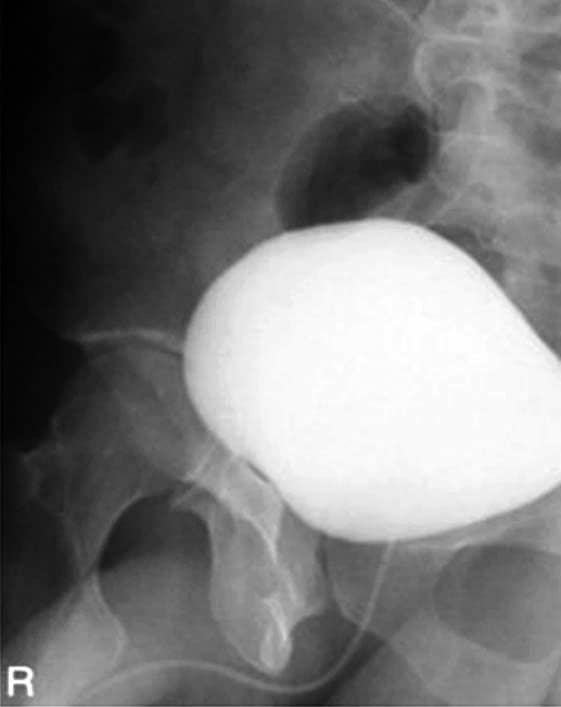

Incidências para a bexiga – Cistografia (AP, OPE, OPD e lateral)

Cistografia 10° a 15° caudal.

Cistografia oblíqua posterior direita em 45°.

Cistografia lateral (opcional) em decúbito lateral esquerdo.

Radiografias contrastadas da bexiga (cistografia) AP axial em 15° caudal e OPD 45°.

Justificativa para realização do exame

Visualizar sinais de cistite, refluxo vesicoureteral e cálculos vesicais.

Principais estruturas demonstradas

No AP – Toda a bexiga sem superposição dos púbis e da sínfise púbica. Nas oblíquas posteriores – A bexiga não deve estar superposta. Na lateral (opcional) – Os quadris e fêmures estarão superpostos.

Fatores técnicos e posicionamento

• DFF: 1m.

• Tamanho do filme/receptor de imagem e sentido: 24x30cm no sentido longitudinal.

• Técnica de referência: 15mAs e 75KV, na mesa para o AP. 20mAs e 75KV para as oblíquas e 48mAs e 90KV para a lateral.

• RC: perpendicular no centro do filme e superior em 5cm à sínfise púbica.

• Posição do paciente e da parte ou região do corpo: paciente em decúbito dorsal, com os braços ao lado do corpo, para o AP; com rotação de 45° a 60° para as oblíquas; e em lateral verdadeira para a posição lateral (opcional).

• Respiração: parar a respiração e expor durante e expiração lenta.

Atenção

Essas incidências radiológicas servem para investigar a bexiga, sendo a técnica lateral usada poucas vezes e servindo de opção para uma investigação mais detalhada ou que gere dúvidas sobre o diagnóstico proveniente das imagens anteriores e principais.